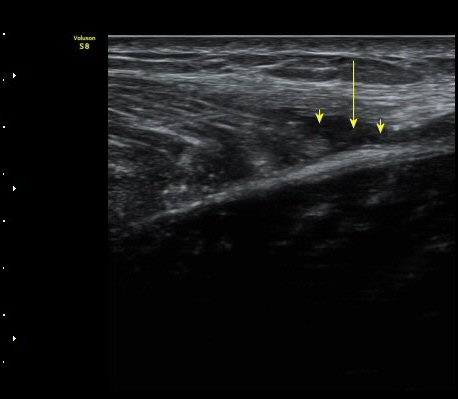

ºñº¹±Ù Ⱦ´Ü¸é°Ë»ç¿¡¼­ ºñº¹±Ù ³»Ãø, °¡Àڹٰ̱ú Á¢ÇÕ ºÎÀ§ÀÇ ÆÄ¿­°ú ¼ö¾× Àú·ù°¡ °üÂûµÊ(±×¸² 4)